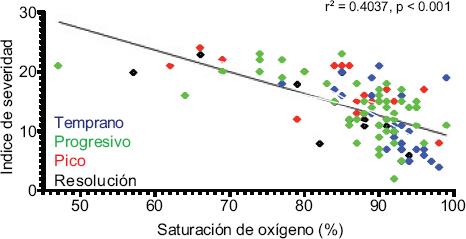

Se realizó una valoración semicuantitativa y cualitativa del patrón tomográfico para establecer una escala de severidad6,7 conforme a las sugerencias de Juárez Hernández et al. (Instituto Nacional de Enfermedades Respiratorias, artículo en prensa, mayo de 2020). La escala de severidad pretende predecir el pronóstico del paciente dependiendo de la extensión de la afectación pulmonar por cada lóbulo y posteriormente se identifica el patrón predominante (Tabla 5). Los resultados se muestran en la Tabla 6. Los datos obtenidos con la escala fueron correlacionados con la saturación de oxígeno para determinar la reciprocidad (Figura 6).

Figura 6 Correlación del índice de severidad versus saturación de oxígeno de acuerdo con la etapa. Existe una relación entre el índice de severidad (por tomografía) y la saturación de oxígeno (r2 = 0.4037, p < 0.001); sin embargo, en el análisis individual se observó que en etapas tempranas (azul) la mayoría de los pacientes presentó saturación de oxígeno > 85%, aun cuando algunos presentaban un índice de severidad alto. En otras etapas se observaron más pacientes con saturación de oxígeno < 80% y en todos ellos el índice de severidad fue severo (> 15 puntos). Una saturación de oxígeno alta no excluye la posibilidad daño pulmonar extenso.

Respecto a la escala de severidad sugerida, es útil únicamente para orientar acerca del grado de afectación del parénquima pulmonar, pues no se encuentra en relación directa con la saturación de oxígeno ni con el cuadro clínico real del paciente, con lo que se comprueba la disociación clínico-radiológica referida en la literatura13 (Figura 6).

Proporcionamos la primera descripción de los patrones tomográficos típicos de la neumonía causada por SARS-CoV-2 en pacientes mexicanos y analizamos la frecuencia con la que se presentan en hombres y mujeres en las diferentes etapas de la enfermedad. Lo anterior permitirá la familiarización de los médicos con los hallazgos tomográficos clásicos para realizar una detección temprana. En nuestra población, el diámetro aumentado de la arteria pulmonar fue un hallazgo común que puede indicar hipertensión pulmonar. Demostramos que las bandas subpleurales aparecen después de la fase aguda de la enfermedad, pero se requiere un estudio prospectivo a largo plazo para corroborar si pueden causar fibrosis pulmonar. Asimismo, se comprobó que la escala de severidad pulmonar sugerida por Juárez Hernández et al. no siempre se correlaciona con el estado clínico del paciente y es útil únicamente para proporcionar una idea de la extensión del compromiso pulmonar y con ello decidir el manejo del paciente.